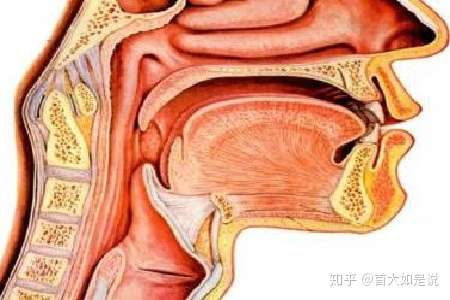

咽喉炎会引发喉癌吗 喉癌的预防 去养生www 7ys Com